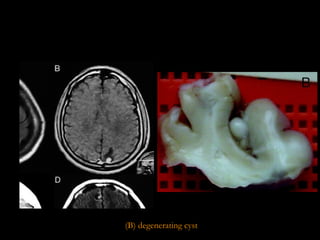

(B) degenerating cyst

STAGES OF NC Cystic or vesicular stage Cyst wall & scolex do not enhance  Cyst is viable & has a well defined, fluid-filled membrane contains only one scolex.  Colloid stage Enhancing walls with perilesional oedema Earliest stage in the involution of the cyst. the fluid contents of the cyst become more turbid and the scolex begins to degenerate. Necrotic, granular stage Characterized by parasite necrosis and surrounding inflammation Gives an appearance of an eosinophilic structure in which the bladder and scolex are in various stages of disintegration Oedema and/or necrosis of the surrounding neural tissue may be present in some cases Fibro-calcified nodule With time, fibrosis develops, progressively occupying the entire lesion D.Sharada et al